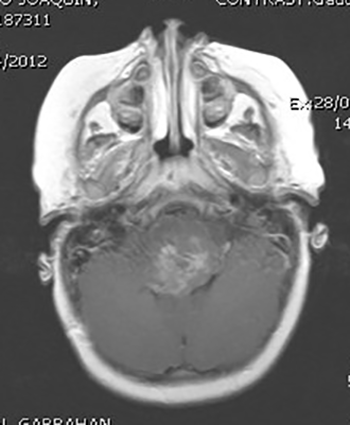

Figura 3:

IRMN T1. Tumor en mescencéfalo heterogéneo, dada la alta morbilidad quirúrgica fue realizada una biopsia estereotáctica dando como resultado astrocitoma de bajo grado.